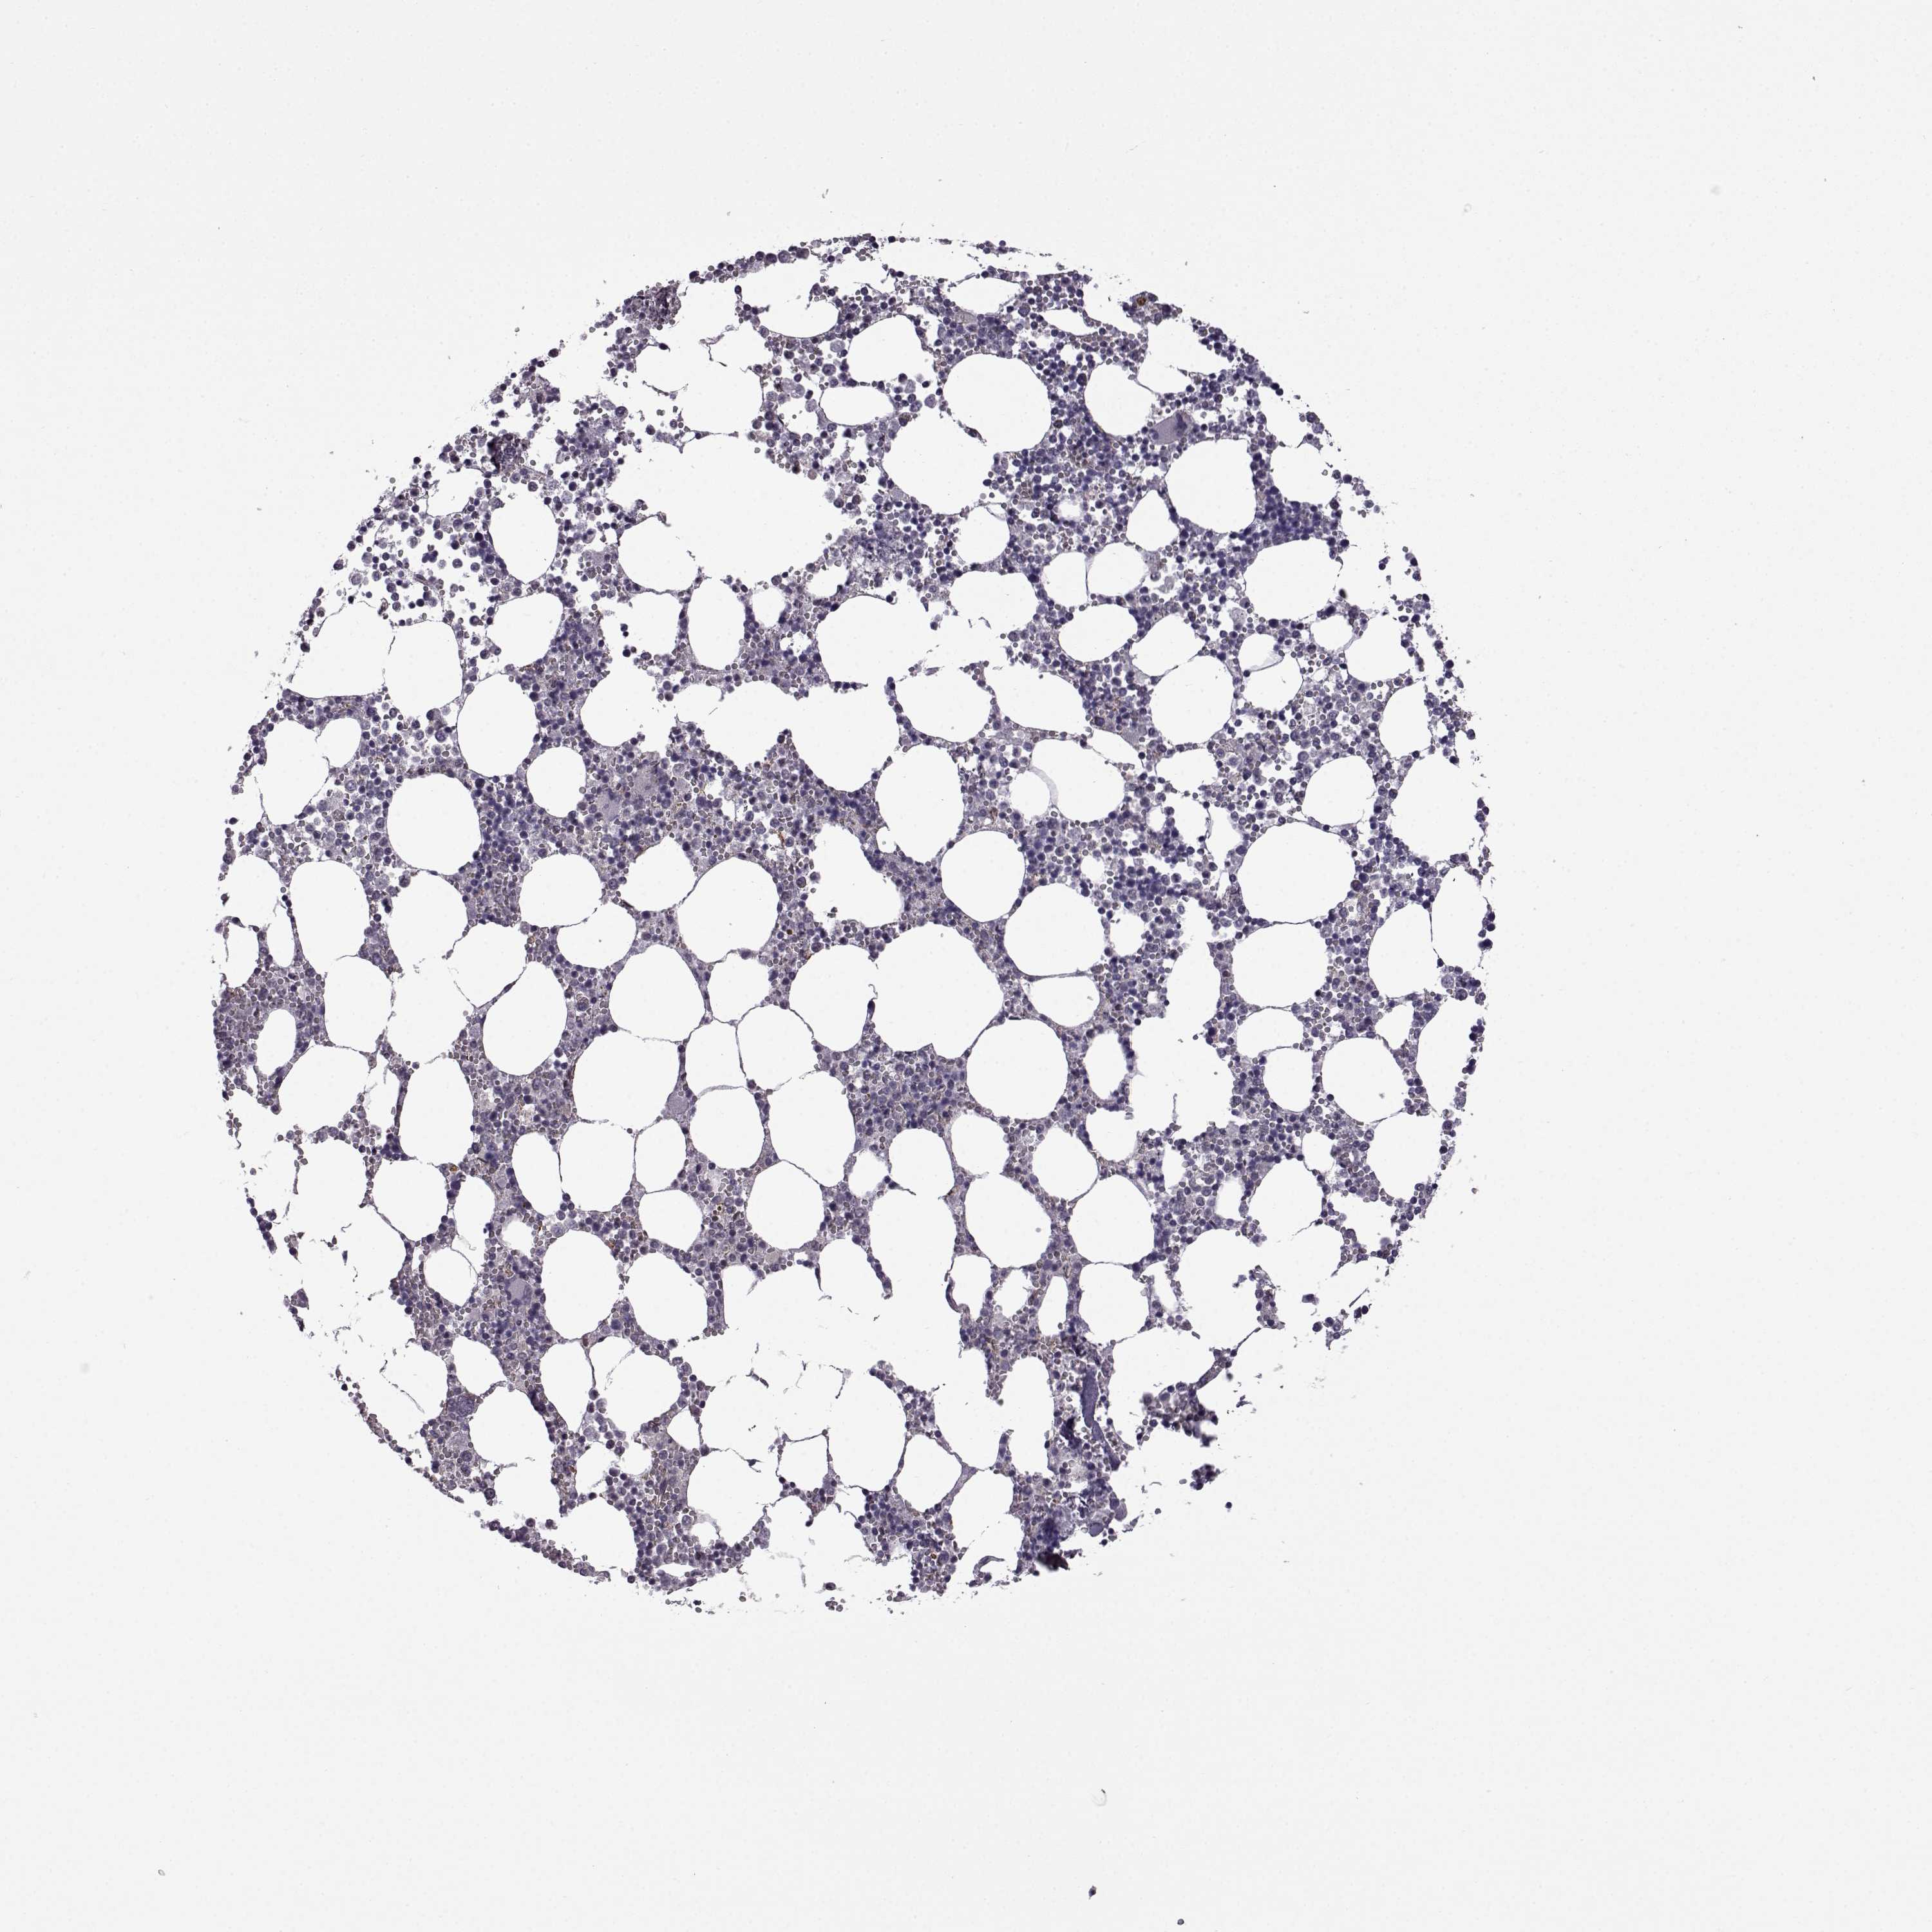

BONE MARROW - Antibody stainingi

Antibody staining in the annotated cell types in the current human tissue is reported as not detected, low, medium, or high, based on conventional immunohistochemistry profiling in selected tissues. This score is based on the combination of the staining intensity and fraction of stained cells. Each image is clickable and will lead to virtual microscopy that enables deeper exploration of all samples and also displays staining intensity scores, fraction scores and subcellular localization as well as patient and tissue information for each sample.

Antibody HPA030665Antibody HPA068563Antibody CAB037231

Hematopoietic cells Not detectedNot detectedNot detected

Information about each individual sample is listed below, including gender, age, a tissue section image and estimated fractions of cell types. nTPM (normalized transcripts per million) values give a quantification of the gene abundance which is comparable between different genes and samples.

Bone marrow sample 97

nTPM: 0.3

Cell types%

Myelopoietic cells:

50

Erythropoietic cells:

30

Lymphocytes:

10

Monocytes:

5

Blastic cells: